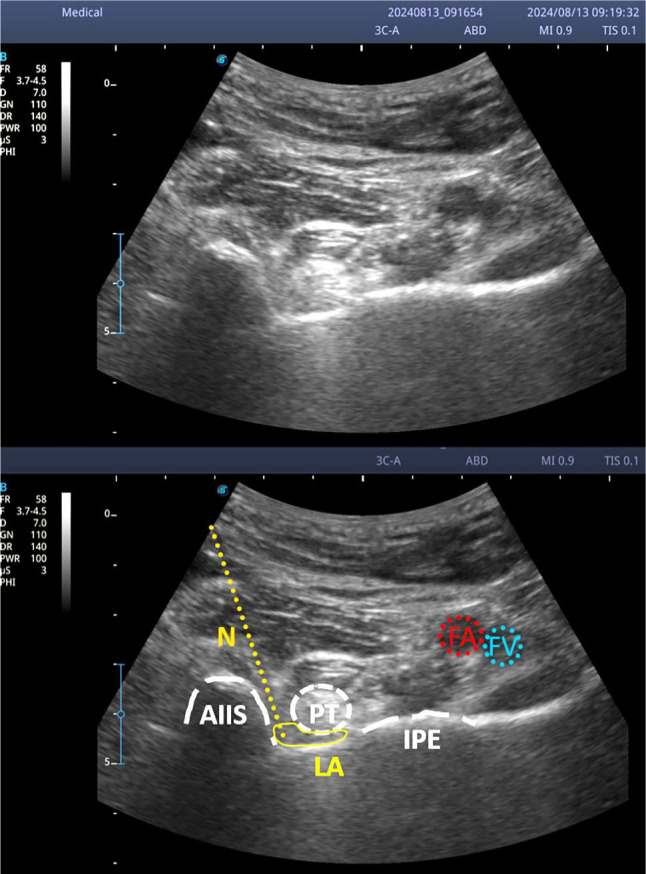

Objectives: The aim of this study was to evaluate the efficacy of pericapsular nerve group block (PENG) and genicular neurolysis performed with ethyl alcohol in the management of pain associated with hip or knee osteoarthritis or persistent postoperative pain following arthroplasty.

Patients and methods: Between October 2023 and June 2024, a total of 89 ambulatory adult patients (70 males, 19 females; median age: 75.5 [IQR: 62.6 to 81.3] years; range: 46.7 to 92.8 years) who visited our pain clinic were retrospectively analyzed. The PENG or genicular nerve neurolysis was performed as appropriate using ethyl alcohol. Median and maximum level of pain according to patient self-report was registered before and after the interventions.